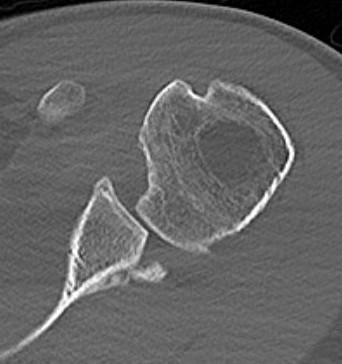

Osteochondral Allograft Reconstruction

Indication

Reverse Hills Sachs defects 25 - 50%

Technique

Case 1: Lesser tuberosity osteotomy, removal comminuted articular fragment, insertion osteochondral allograft

Case 2: Osteochondral allograft with anchor repair of subscapularis

Results

- systematic review of McLaughlin and humeral head allograft for reverse Hill Sachs

- 14 studies and 150 patients

- no difference in outcomes between 2 groups

- OA: McLaughlin 11%, allograft 21%